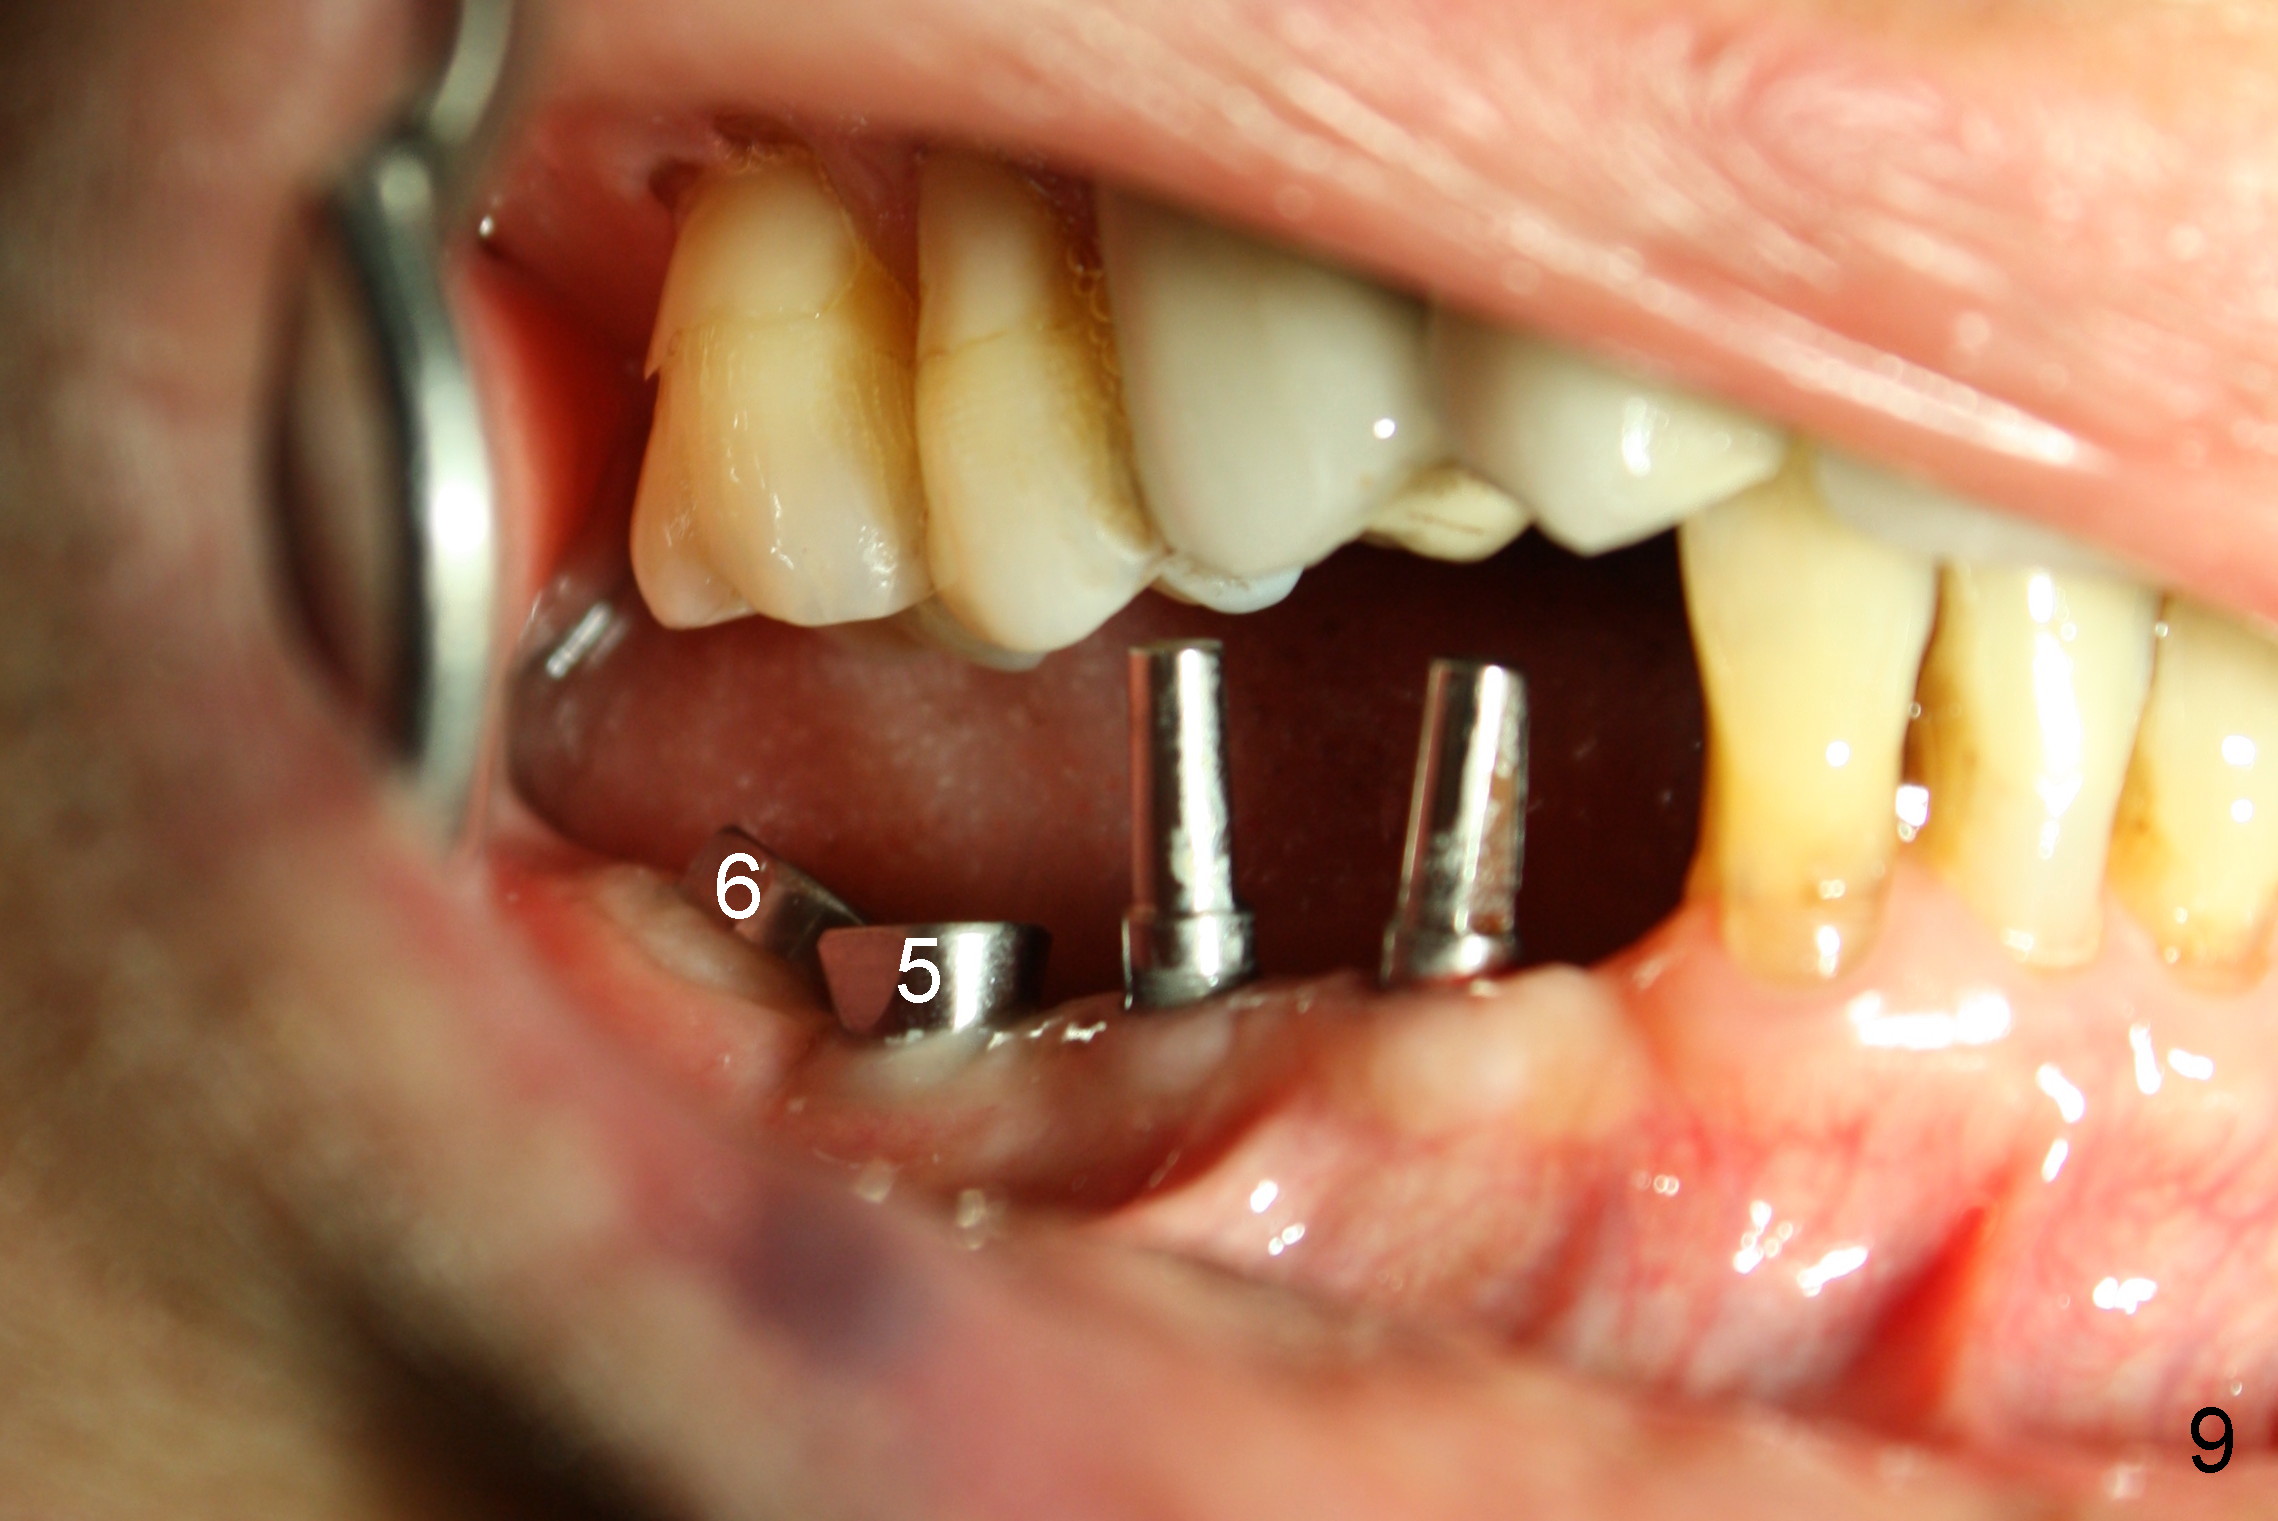

The lower right bridge (from canine (Fig.2: 3) to 1st molar (Fig.1: 6)) fails while a 77-year-old man is undergoing chemotherapy for urinary bladder cancer.  The abutments of the bridge are extracted without plan for implants (Fig.4).   Four months later, the patient returns for implants (Fig.3), but the ridge is narrow (Fig.5).  While 2 of 3x14 mm 1-piece implant are placed at the canine and 1st bicuspid sites, 2 piece ones at the 2nd bicuspid and 1st molar sites (Fig.6: 3.5x11 mm, 5x14 mm).  Soft (Fig.7-10) and hard (Fig.11) tissues heal 1 week (Fig.7) and 4 months (Fig.8-11).  There is minimal bone resorption 1 year 7 months post cementation (Fig.12,13, non-splinting).  It appears that narrow diameter implants are a valid solution to narrow ridge at the sites of the lower canine and premolar.  As long as there are enough implants for function, the crowns are not necessary to be splinted.  Surprisingly, the patient starts flossing after implant restoration.  Retrospectively an immediate provisional bridge should have been fabricated.